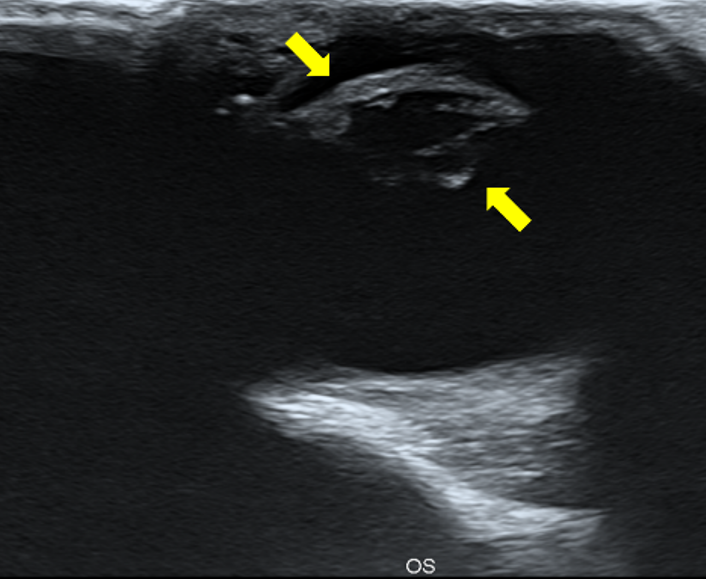

.png)

사진2. 초음파 검사를 통한 penetrating injury 검사. 검사 시 안구가 압박 되지 않도록 하며 또한 흥분으로 인하여 일시적으로 각막이 fibrin에 의하여 막힌 부위가 터지지 않도록 주의하여야 한다.